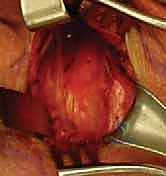

الخطوة 2: كشف المفصل وحماية الهياكل الحيوية

هذه هي المرحلة الأكثر حساسية. يتم كشف نهاية عظم الترقوة وعظم القص. يستخدم الدكتور هطيف أدوات جراحية دقيقة لحماية الأوعية الدموية الكبرى والقصبة الهوائية الموجودة خلف المفصل (تُستخدم أحياناً مبعدات خاصة لحماية هذه الهياكل).